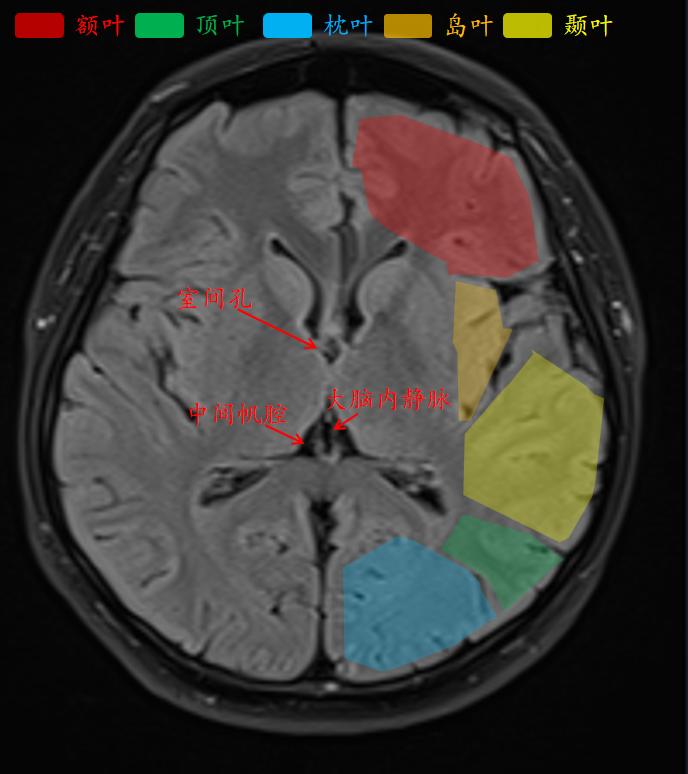

外侧沟把额叶、颞叶和顶叶分开。

颞叶的主要功能主要是听觉功能。

枕叶的主要功能是视觉功能。